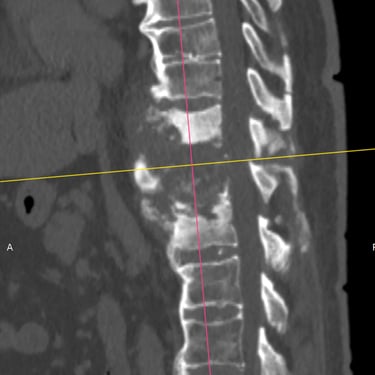

🧠Listesis Lumbar L5–S1 por Fractura Ístmica: Estabilización con FTP y TLIF.

La listesis L5–S1 por fractura ístmica causa inestabilidad y dolor. El tratamiento quirúrgico con FTP y TLIF permite descompresión neural y estabilización vertebral, mejorando la función y calidad de vida.